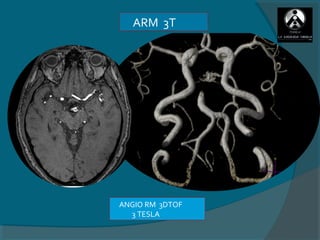

ARM 3T

ANGIO RM 3DTOF

3 TESLA

3D TOF   VOLUME   RENDERING